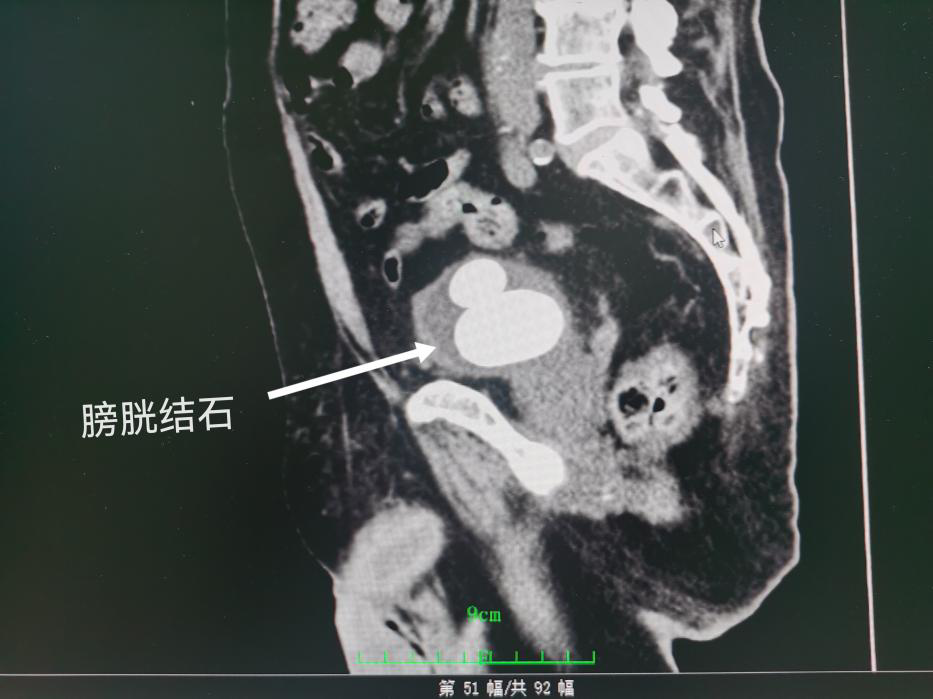

林爷爷(化名)是一名98岁的高龄患者,因反复尿痛、肉眼血尿、十余年排尿困难来医院就诊,经检查发现膀胱内有两枚7CM“鹅卵石”样的结石,占据了整个膀胱的空间。不仅如此,左侧输尿管下段也藏有两枚小结石。

手术由泌尿外科学科带头人谢群主任医师亲自主刀,采用pilipili 新引进的大功率钬激光经尿道粉碎结石,由于结石较大,手术历时3小时,术中几乎无出血,在麻醉科的精心管理下,患者顺利渡过手术难关,目前已平安出院。